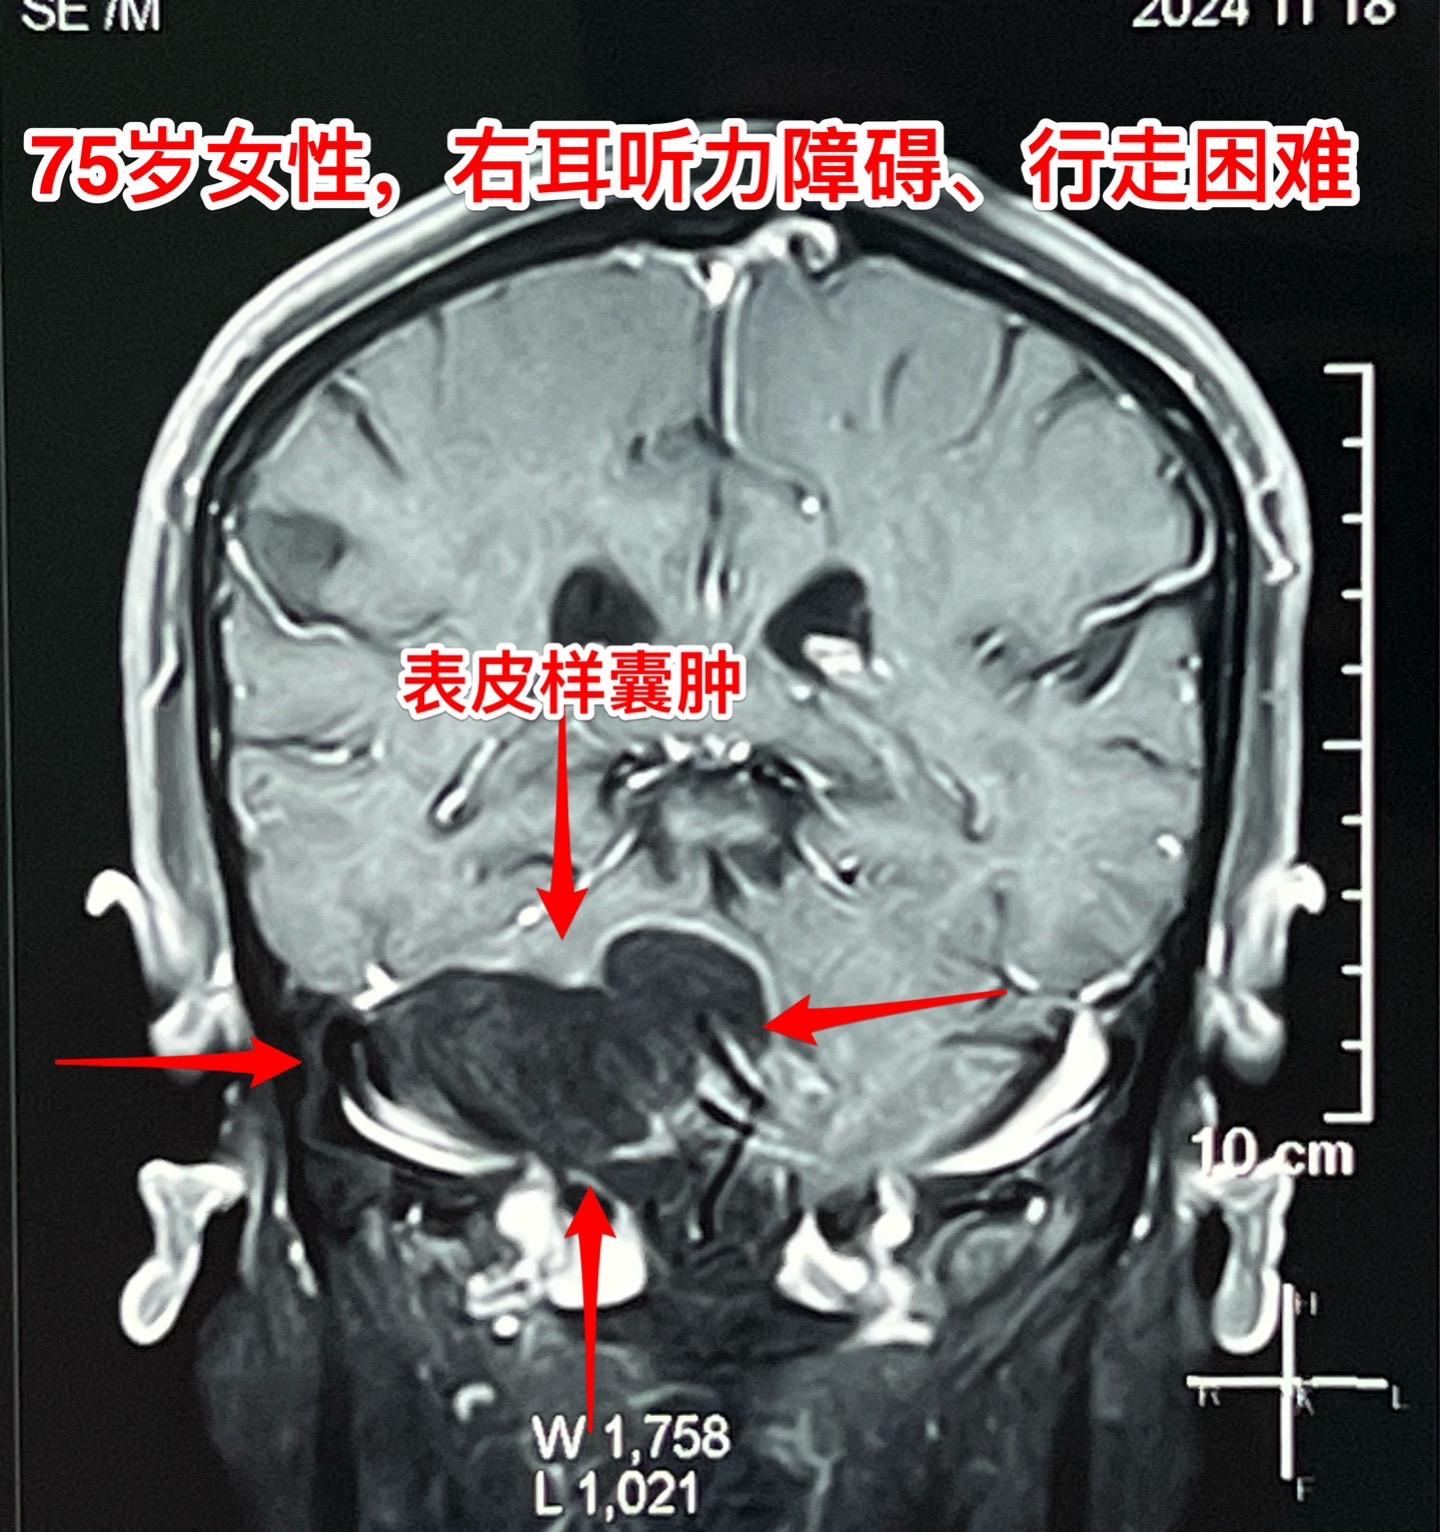

75岁的老奶奶决定接受开颅手术了!75岁的辽宁省海城老奶奶在5年前就曾发现脑部长了一个可疑肿瘤(怀疑为表皮样囊肿或者胆脂瘤),右耳听力下降。当时在沈阳就医,医生建议作手术,但是考虑到病人已经70岁高龄了,手术风险很大,当时老人和家属就决定不作手术。 在五年时间内老人的病情在慢慢加重,逐渐出现行走困难,生活质量越来越差。儿女孝顺,都想方设法地希望能够改善老人的生活质量! 老人的女婿有个表哥,张先生,患颅咽管瘤,曾经在2016年因颅咽管瘤复发了在我这里作了手术。手术后8年了,